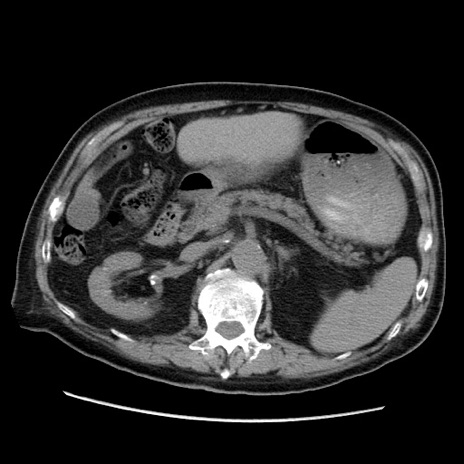

症例21(横断像)

【症例】70歳代男性

【主訴】腹痛

【現病歴】肝硬変・肝細胞癌にてかかりつけの方。約9時間前に食後より腹痛出現。症状が徐々に増悪し、嘔吐出現したため来院。

【既往歴】肝硬変、肝細胞癌(RFA、TACE後)

【身体所見】意識清明、表情苦悶様、BT 36℃、BP 129/78mmHg、P 88bpm、SpO2 97%(RA)、右上腹部から心窩部にかけて圧痛あり、反跳痛なし、筋性防御あり。

【データ】WBC 5800、CRP 0.16